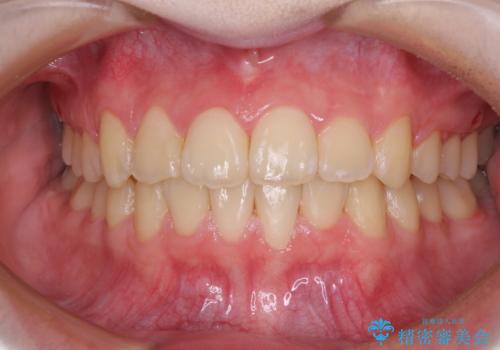

前歯をきれいに整えたい ワイヤー装置での非抜歯矯正

治療途中で大学受験があり、来院できない時期がありましたが、2年以内で満足のいく歯並びを達成することができました。